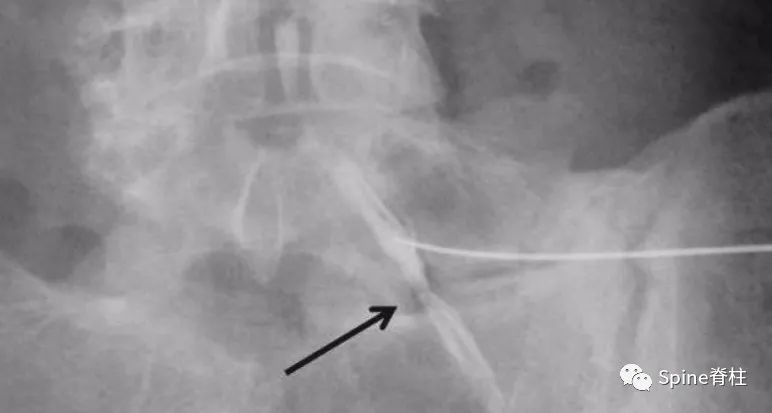

60岁,男性患者,因进行性、严重的接近L5根支配区的下肢放射痛3周入院,诊断为背侧硬膜外椎间盘突出症。

腰椎间盘突出症状表现,腰椎间盘突出症疼痛最佳止痛方法

L2-L3水平背侧硬膜外占位,磁共振增强提示病灶边缘强化(c)

背侧硬膜外椎间盘突出示意图

突出的椎间盘迁移至硬膜外后间隙,硬膜外背侧和腹外侧均有异常软组织(椎间盘内容物或肉芽组织)。L3-4是最常见的节段,其次是L4-5。

背侧硬膜外椎间盘突出症(dorsal epidural disk herniation)常发生在常L3-4,其次为L4-5,易误诊为滑膜囊肿、血肿、脓肿或肿瘤。常急性发病且常伴发马尾神经综合征。